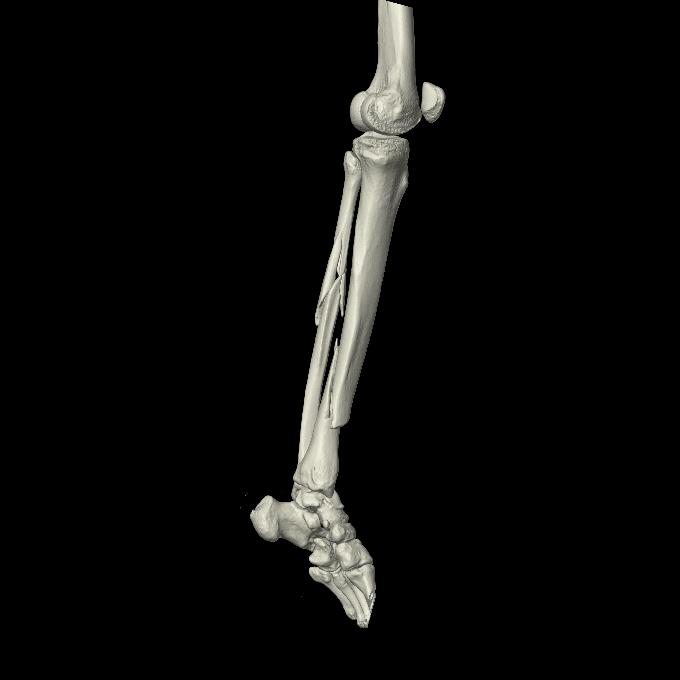

102803 1/12(キウスなし) 1/27 左下腿 4R 30歳女性 左脛骨軸内釘